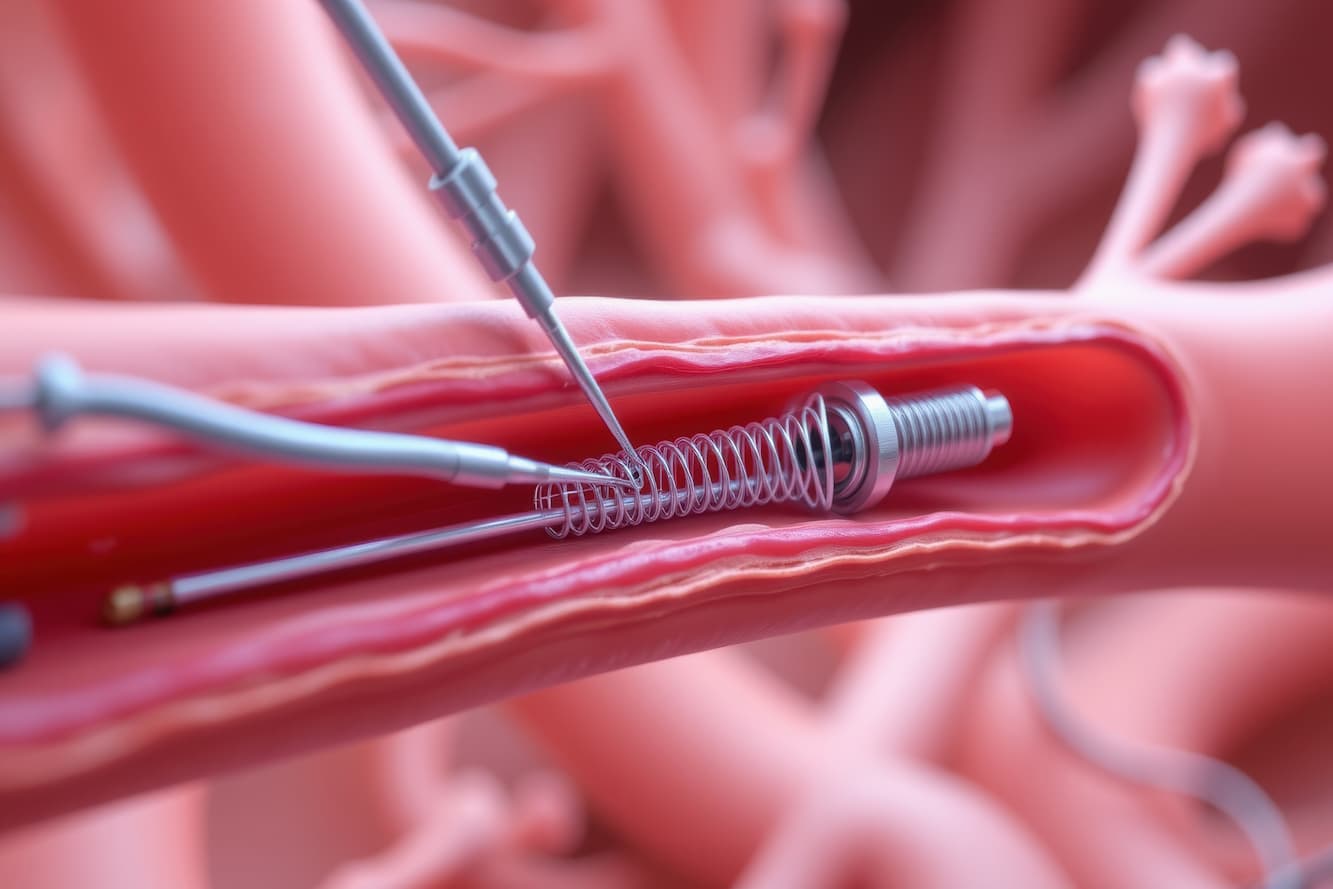

Cardiology plays a pivotal role in maintaining heart health, covering everything from regular check-ups to complex procedures. We partner with esteemed cardiologists from top hospitals.

Cardiology plays a pivotal role in maintaining heart health, covering everything from regular check-ups to complex procedures. We partner with esteemed cardiologists from top hospitals.